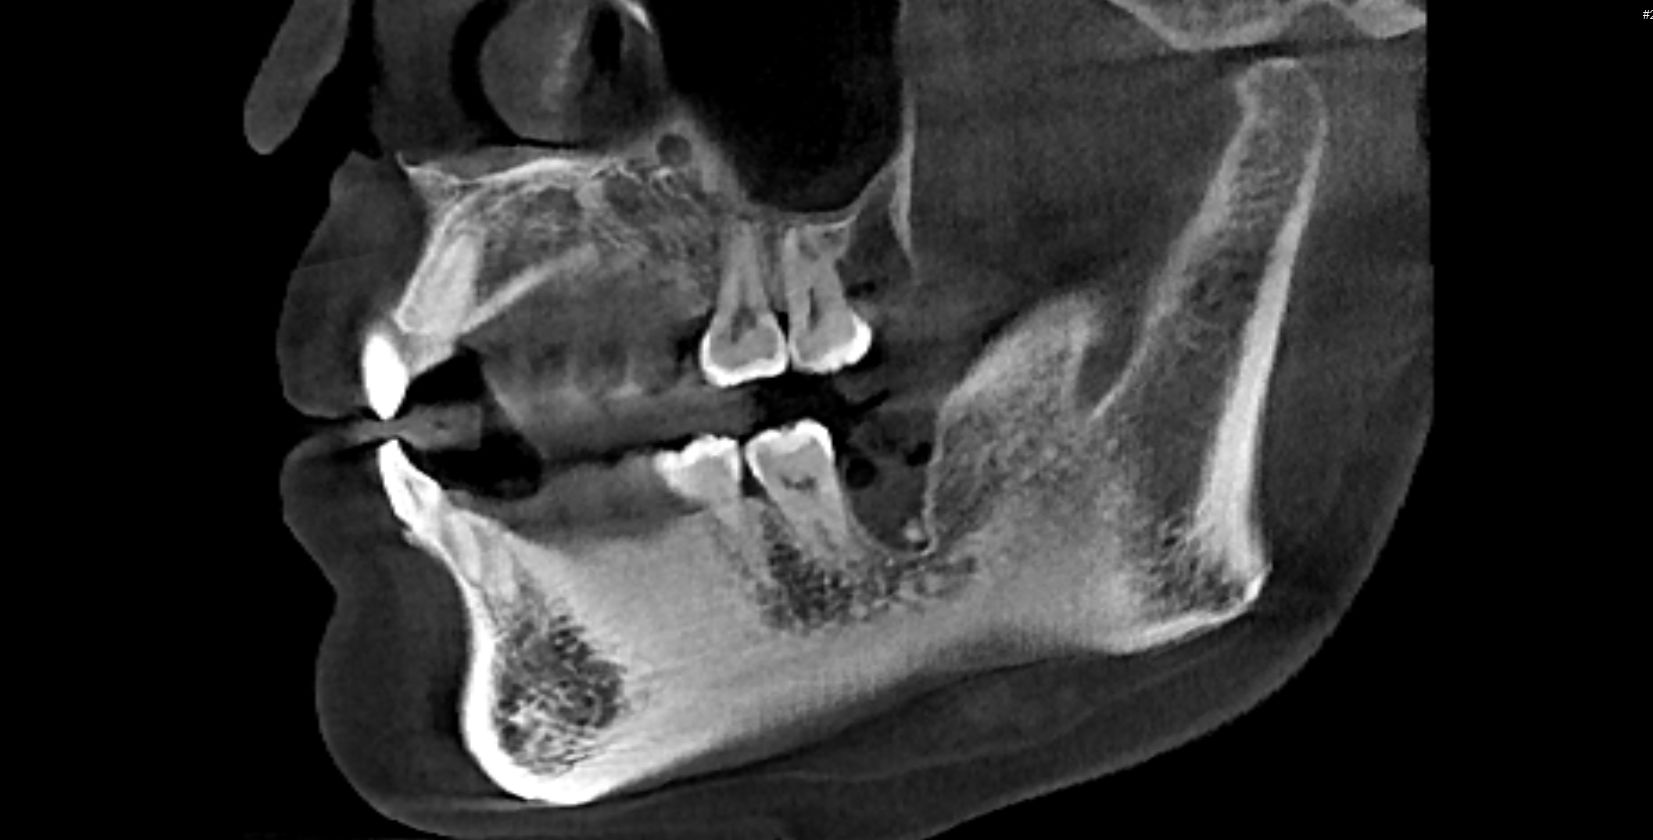

- 首先要找靠谱的医生去面诊,详细了解一下自己 的情况,面诊检查【拍片、照相、取牙模】 后面有详细介绍

PS: 前期准备工作包括(全景片 ,头颅侧位片 ,CT ,6张口内 照片,6张面相照 , 模型,补牙,洁牙…)